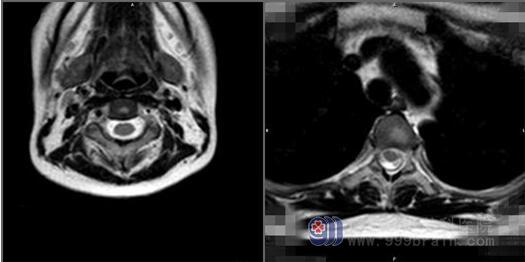

MR全脊柱拼接平扫+增强提示脑干腹侧、胸腰髓周缘多发点线样异常强化影。